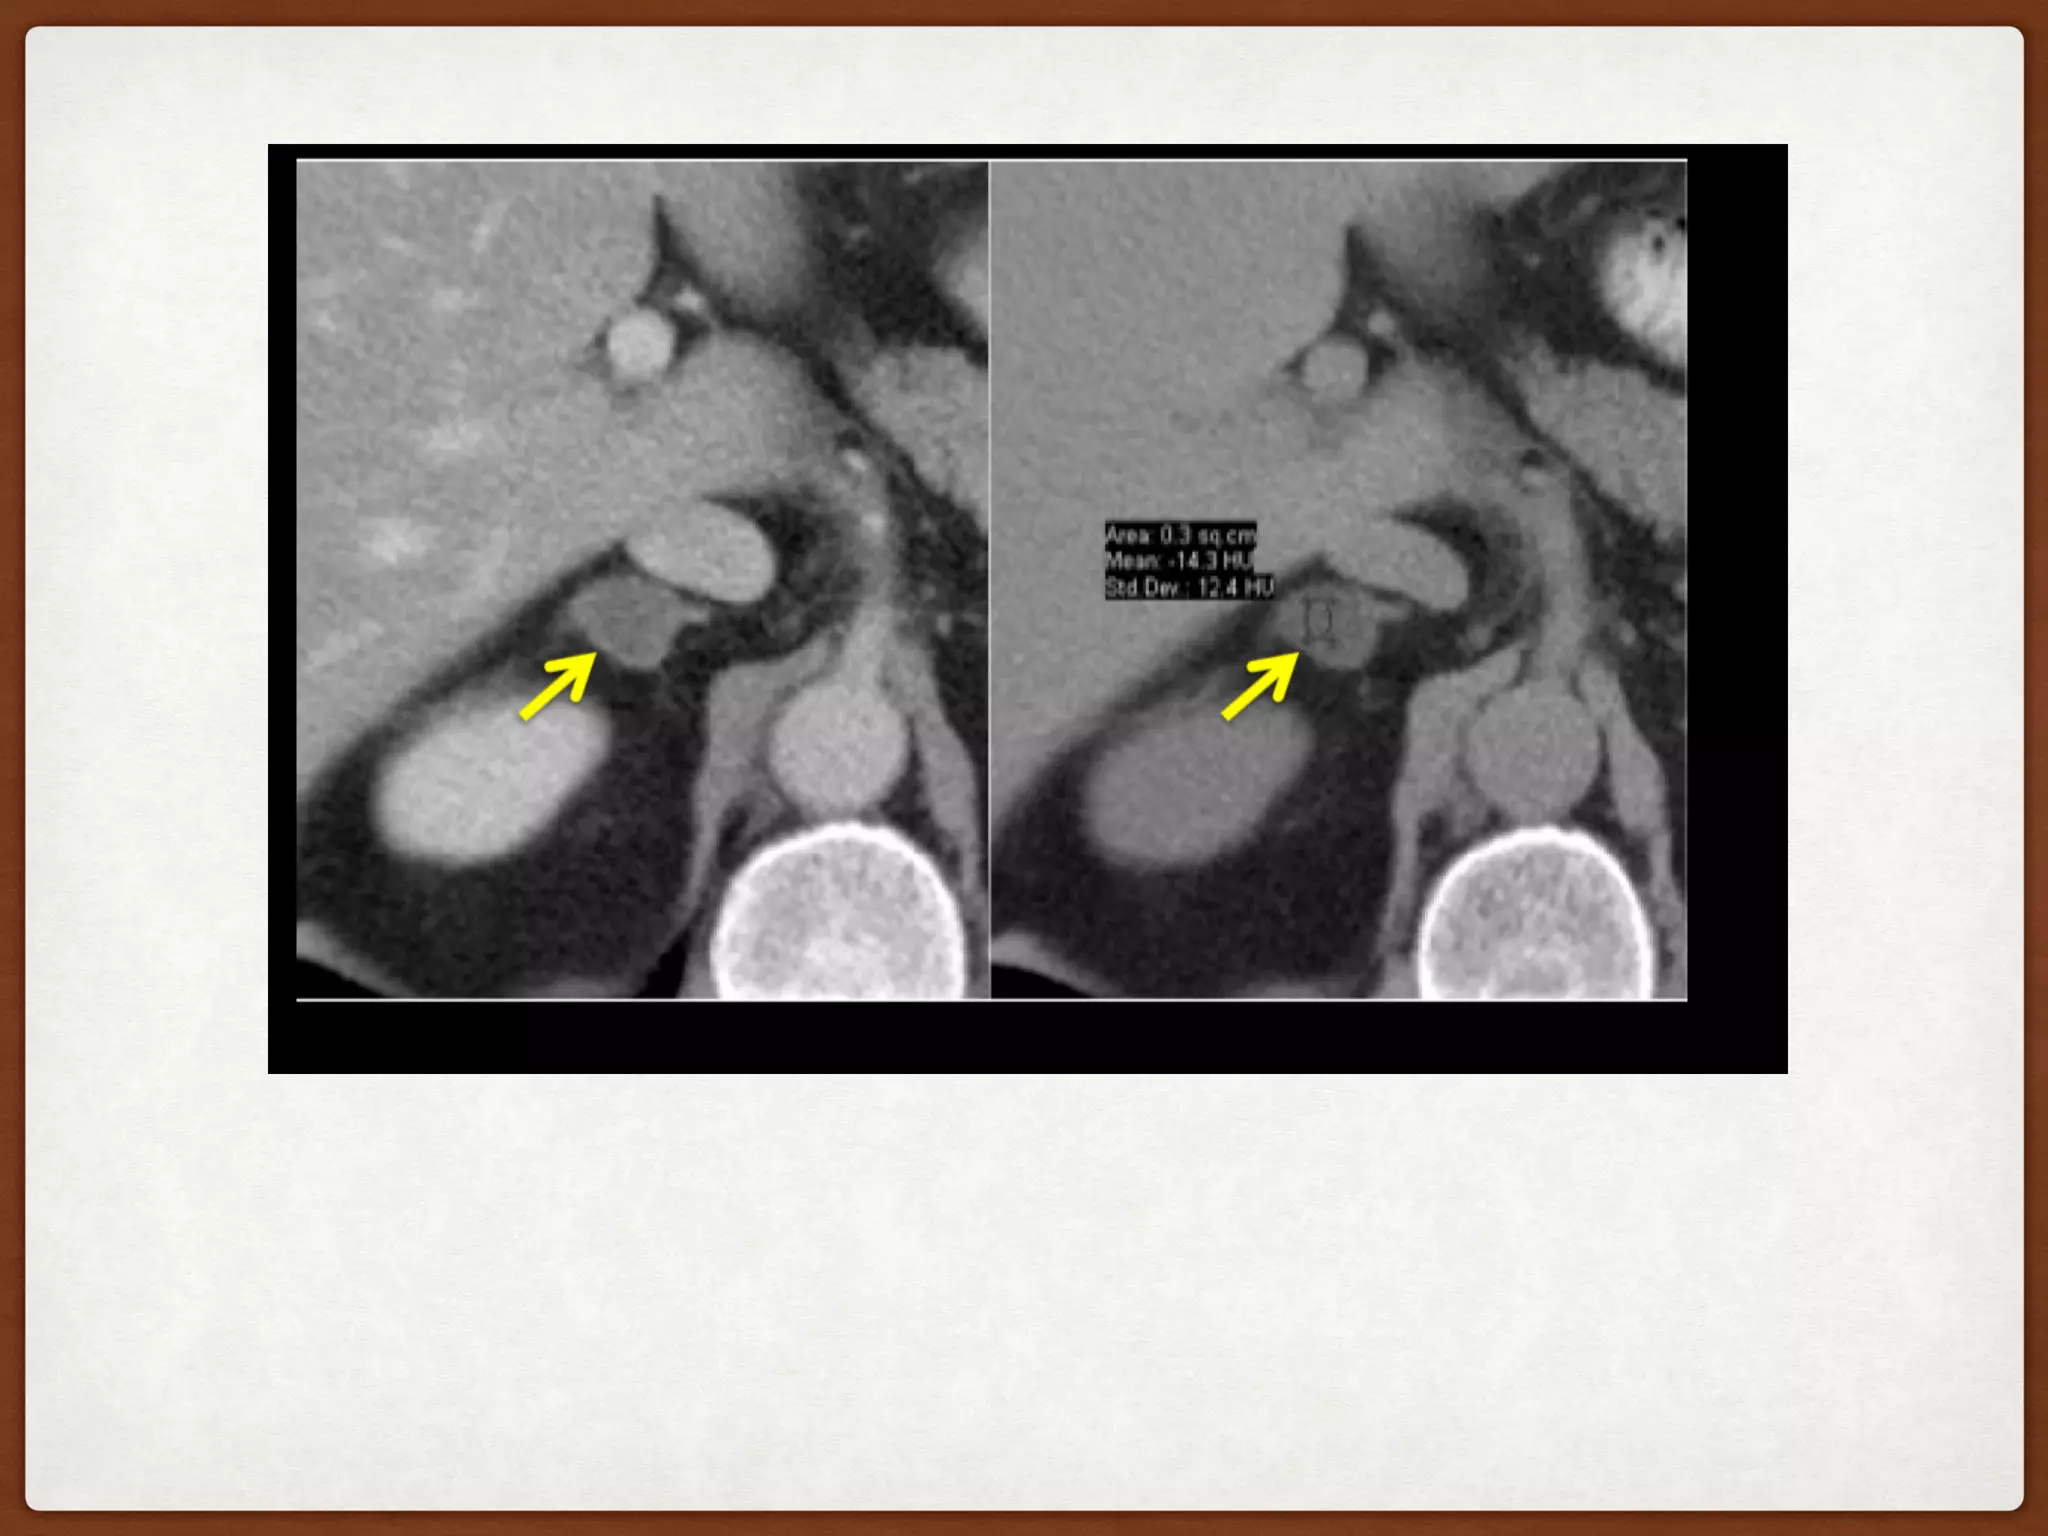

Fig. 7: Right adrenal

adenoma.

Spontaneous density :

41HU.

Enhanced density at 1

min : 90 HU

Delayed density at 10

min : 55 HU

Absolute Wash Out :

71.4% (>60%)

Relative washout:

80%(>40%)